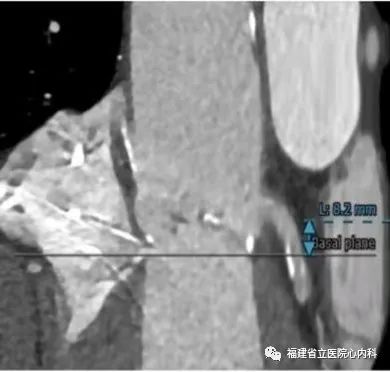

该病例是三叶瓣,中度钙化,法式窦结构可,但是左冠状动脉开口低,左冠瓣瓣叶冗长,预测掀起的瓣叶可能超过冠脉开口上缘,术者在术前通过CT精准评估冠脉风险,制定详尽的介入治疗策略,术中通过25号球囊预扩进一步确认冠脉情况,最后将29号瓣膜精准植入预期位置,避免冠脉风险,达到预期手术效果。

瓣环

窦部

左冠高度:8.2mm

瓣叶长度:14.9mm

球囊预扩张

植入L29瓣膜